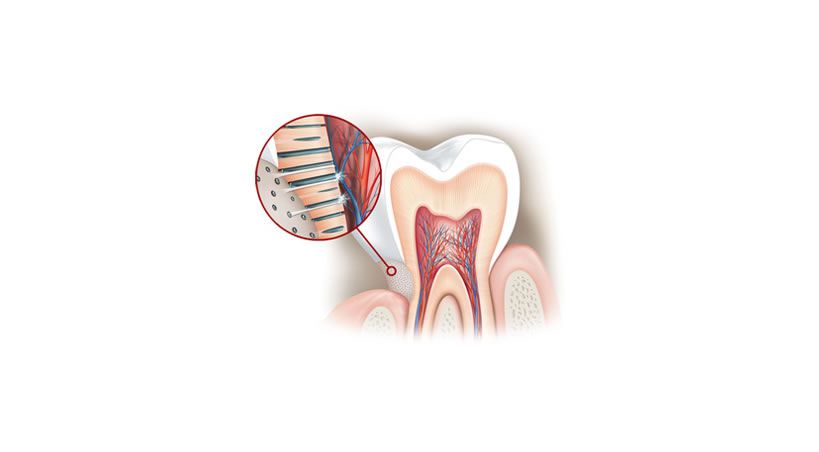

La dentina tiene tubos diminutos ("túbulos") que contienen los extremos de los nervios y están llenos de líquido. Beber o comer alimentos y bebidas calientes, frías o dulces puede provocar que este líquido se mueva. El movimiento de este líquido hace que los extremos de los nervios reaccionen como respuesta, provocando un pinchazo molesto o un dolor breve y agudo.